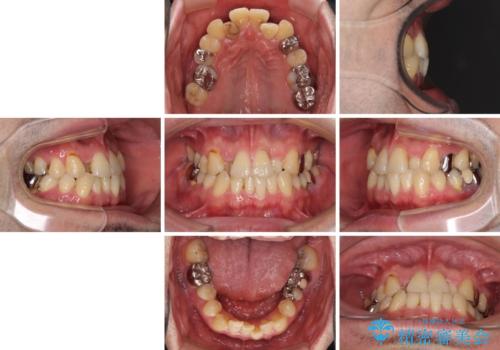

- 奥歯の痛みと前歯のデコボコを気にして来院された患者様です。

左右下顎の大臼歯は、ともに歯根が破折しており、抜歯が必要な状態でした。

放置したことで炎症による骨吸収が顕著であるため、骨造成を併用してインプラント埋入を行うこととしました。

咬み合わせは受け口傾向であり、上顎前歯の叢生が顕著であったことから、第1小臼歯抜歯による矯正治療も検討しましたが、下顎大臼歯を左右ともに抜歯するため、非抜歯による矯正治療を行うこととしました。